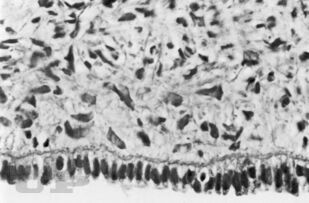

Руководство посвящено прижизненной морфологической диагностике опухолей яичников. В нем приводятся клинико-морфологические характеристики доброкачественных, пограничных и злокачественных новообразований, а также неопухолевых процессов, которые нередко могут имитировать опухоли яичников. Наибольшее внимание уделено дифференциальной диагностике этих заболеваний. Отдельная глава посвящена эмбриогенезу и возрастным особенностям яичников, знание которых существенно расширяет дифференциально-диагностические возможности. Изложение основного материала сопровождается описанием конкретных правил обработки биопсийного и операционного онкологического материала.